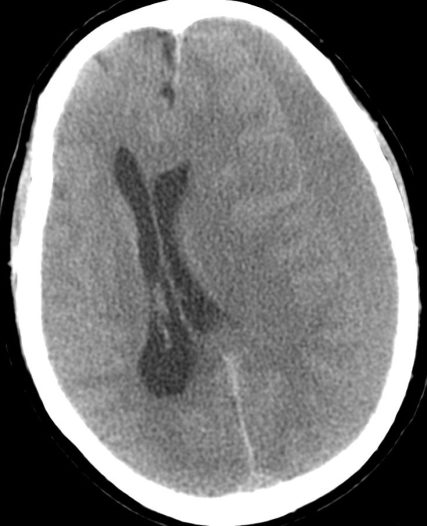

Hemorragia Intraventricular.

- La hemorragia intraventricular se origina por la rotura de las venas subependimarias a lo largo de la superficie de los ventrículos o por extesnión directa de una HSA o de un hematoma parenquimatoso al sistema ventricular.

- Puede ocasionar hidrocefalia.

2- Herniaciones encefálicas

Subfalcina:

- Se produce la herniación de la circunvolución del cíngulo a través de la hoz.

- Puede producir compresión del asta y atrio del ventrículo ipsilateral.

- El VL contralateral puede dilatarse por obstrucción del agujero de Monro.

- Infartos del territorio anterior por compresión de la ACA y venas profundas.